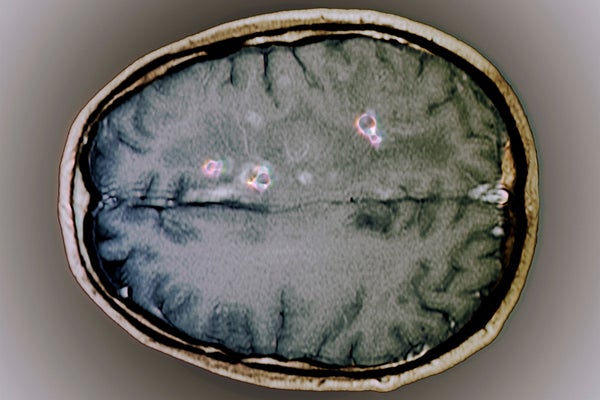

Tapeworm cysts in the brain. Magnetic resonance imaging (MRI) scan of an axial section through the brain of a 25 year old patient showing cysts (neurocysticercosis, purple) from a tapeworm infection. The cysts have been highlighted by the injection of gadolinium contrast medium.

Magnetic resonance imaging (MRI) scan of an axial section through the brain of a 25-year-old patient showing cysts (purple) from a tapeworm infection.

WHITE: The disease from infection with T. solium in the tissues is called cysticercosis, and when it infects the brain, the disease is called neurocysticercosis. In most places [in the body] the larvae don’t cause a lot of problems and end up dying. Those that end up in the brain can survive for a few years, and they usually do not cause a lot of problems. The cysts, these little round, balloonlike structures, are about a centimeter in diameter and are clear, fluid-filled sacs. Sometimes the cysts can become big enough that if they get into the fluid around the brain, called the cerebrospinal fluid (CSF), they can get stuck at little openings in the brain and block the flow [of CSF]. That leads to hydrocephalus [swelling of the brain], and that’s often fatal unless the patient undergoes emergency surgery. But usually the cysts don’t cause a lot of problems—it’s the inflammatory response that you get when [the larvae] are starting to die and dying that can cause problems—particularly seizures.

The [Centers for Disease Control and Prevention] actually has some really striking images of what it looks like when someone has neurocysticercosis. There are these cysts, or little balled-up eggs, in the brain—it has a very Swiss-cheese appearance.